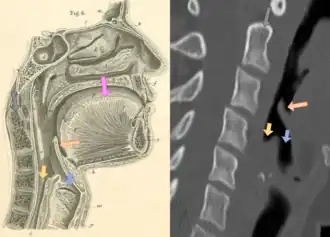

| Neck X-ray showing thumbprint sign | |

Epiglottitis was historically mostly caused by infection by H. influenzae type b (commonly referred to as "Hib").[1] Following the introduction of the Hib vaccine, pediatric cases of epiglottitis fell from 3.47 cases per 100,000 children in 1980 to 0.63 cases in 1990[8] such that it is now more often caused by other bacteria, most commonly Streptococcus pneumoniae, Streptococcus pyogenes, or Staphylococcus aureus.[1] Predisposing factors include burns and trauma to the area.[1] The most accurate way to make the diagnosis is to look directly at the epiglottis.[3] X-rays of the neck from the side may show a "thumbprint sign" but the lack of this sign does not mean the condition is absent.[1]

CT imaging showing the "halloween sign" -

Left column: Normal epiglottis. Right column: Epiglottitis. -

Imaging

On lateral C-spine X-ray, the thumbprint sign describes a swollen, enlarged epiglottis.[11] A normal X-ray, however, does not exclude the diagnosis.[11] An ultrasound may be helpful if specific changes are present, but its use (as of 2018) is in the early stages of study.[11]

On CT imaging, the "Halloween sign" describes an epiglottis of normal thickness. It can safely exclude the acute epiglottitis. Furthermore, CT imaging can help to diagnose other conditions such as peritonsillar abscess or retropharyngeal abscess which have similar clinical features.[23]